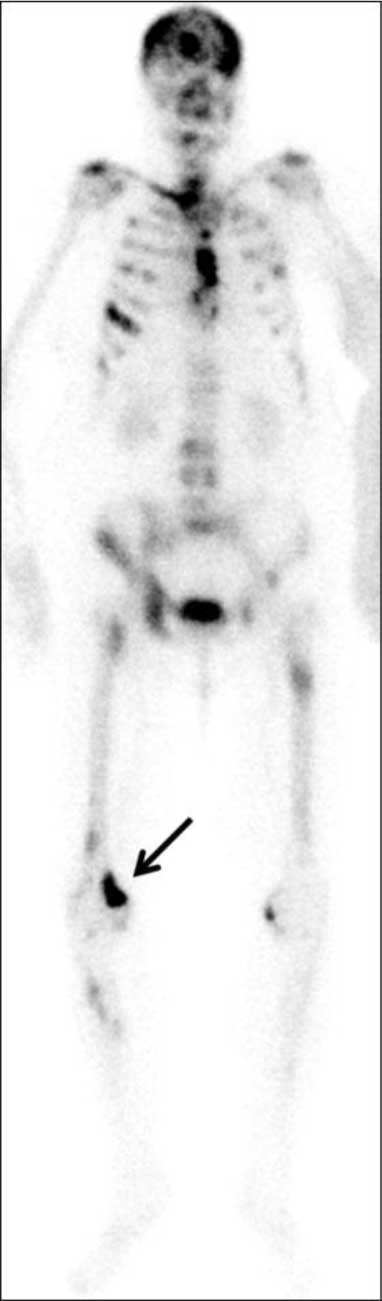

Skeletal scintigraphy confirmed a metabolically active focus in the same location (Figure 2) and revealed multiple other skeletal metastases.

Figure 2

Skeletal scintigraphy – corresponding metabolically active lesion in the right femur (arrow) and multiple other widespread skeletal metastases.